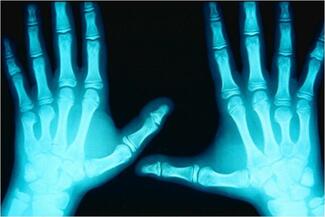

This retrospective review evaluates porcine acellular dermal xenograft interposition for failed trapeziometacarpal arthroplasty, demonstrating improved pain, function, and radiographic outcomes without complications.

Michael C. Doarn, MD; Mariel McLaughlin McArthur, MD; John J. Fernandez, MD